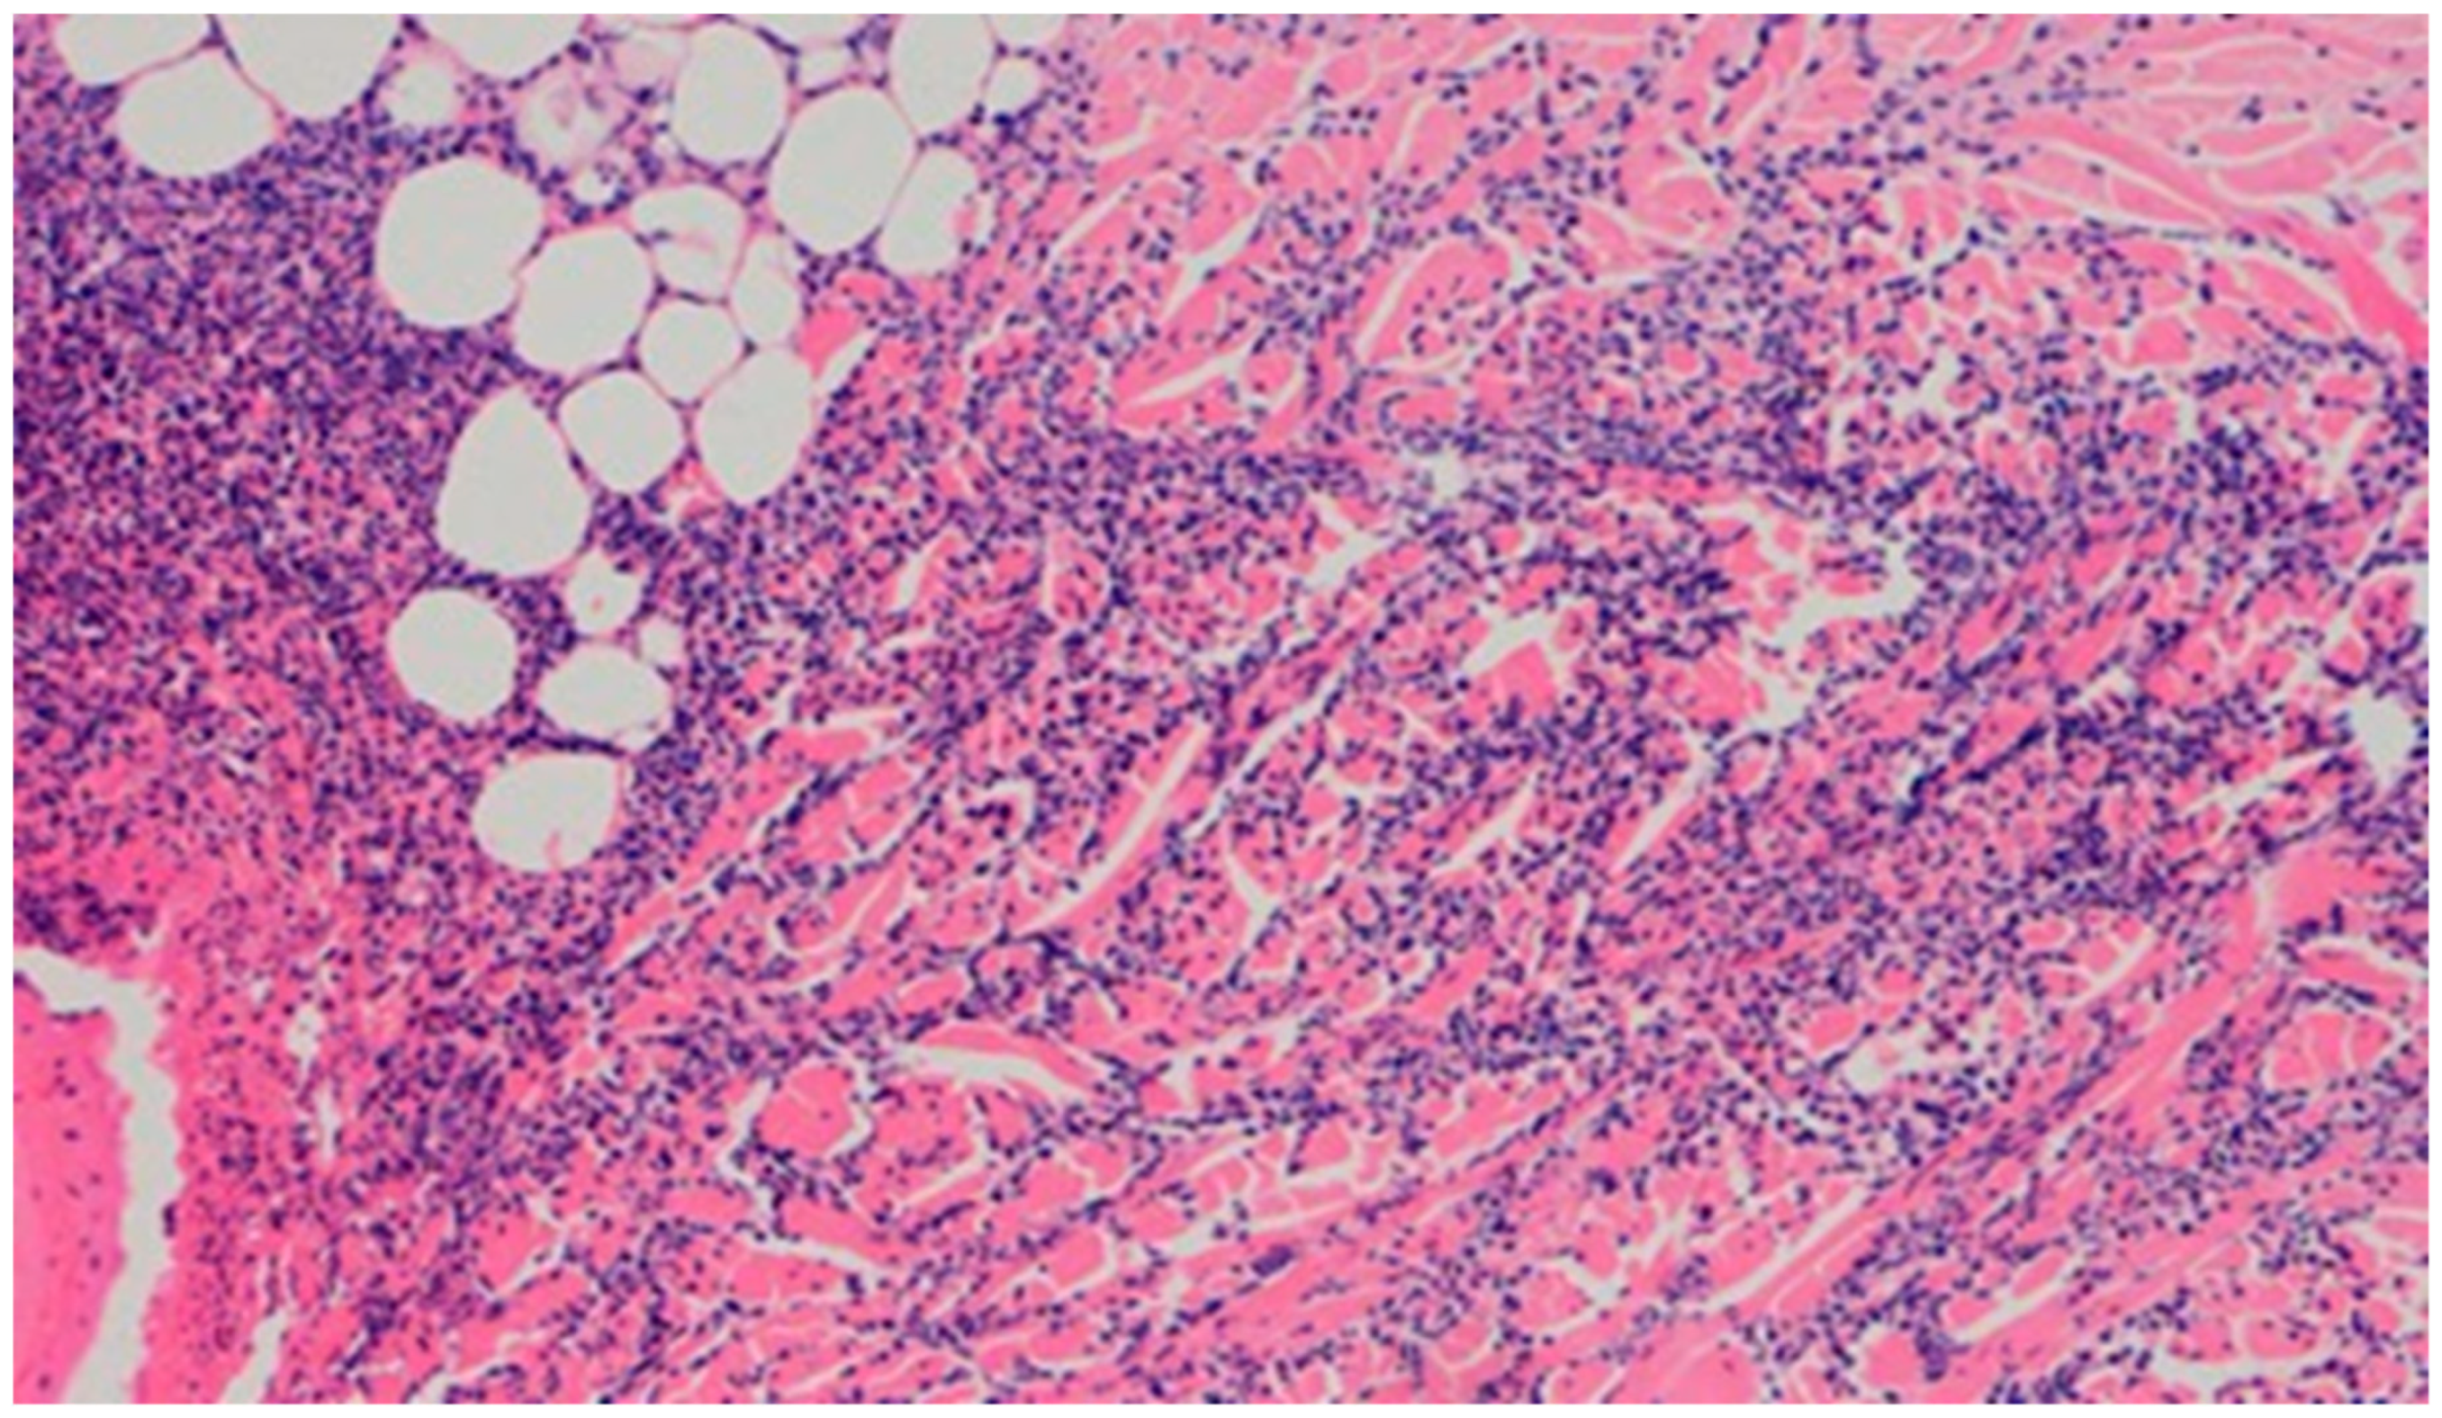

The wound from the experimental group D2, treated with the 1% propolis ointment, showed a regression of inflammation. The wound began to show a slight epidermization only on day 20. There was also a decrease in neovascularization, from high on day 15 to low on day 20, and no superficial necrosis was found. Wound D3, treated with a mixture of 1% propolis and 1% nanosilver, showed no changes on day 20 in the intensity and type of the inflammatory infiltration. Just like the wound in group D2, it was characterized by a slight epidermization only on day 20, with the simultaneous development of superficial necrosis, from being slight on day 15 to large on day 20. The wound was highly neovascularized. In the wound from the control group K, treated with sulfathiazole, the intensity and type of the inflammatory infiltration did not change on day 20, and additionally, epidermization was inhibited. The histopathological findings from day 20 are presented in Table 11 and Figure 20 and Figure 21.

Figure 21. Focal, detachable necrosis on the epidermal skin lesion. Under the epithelium, a low-density lymphocytic inflammatory infiltration (40×, H-E) in the wound treated with the 1% propolis ointment on day 20 is visible.